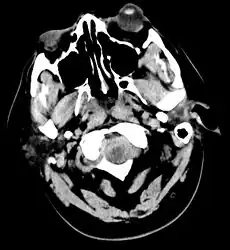

CT scan of the brain showing subarachnoid hemorrhage as a white area in the center and stretching into the sulci to either side (marked by the arrow)

The modality of choice is computed tomography (CT scan), without contrast, of the brain. This has a high sensitivity and will correctly identify 98.7% of cases within six hours of the onset of symptoms.[28][4] A CT scan can rule out the diagnosis in someone with a normal neurological exam if done within six hours.[29] Its efficacy declines thereafter, and a lumbar puncture is also recommended.[1][4] Magnetic resonance imaging (MRI) is more sensitive than CT after several days.[5]